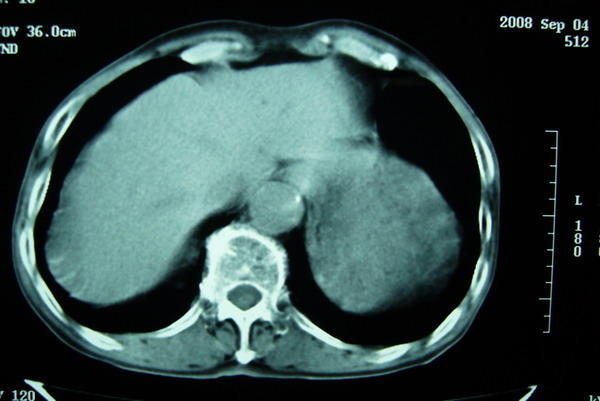

标题: CT15579:男 86岁 咳嗽 咳少量白痰 发热2天 吸烟史60年 [打印本页]

标题: CT15579:男 86岁 咳嗽 咳少量白痰 发热2天 吸烟史60年

右上周围型肺癌,慢支,肺气肿。

分叶及少量边缘性钙化,老年人,周围性肺癌首先考虑。

右上肺一不规则团块,边缘有分叶和毛刺,纵隔有淋巴结肿大。右肺周围性肺癌首先考虑。